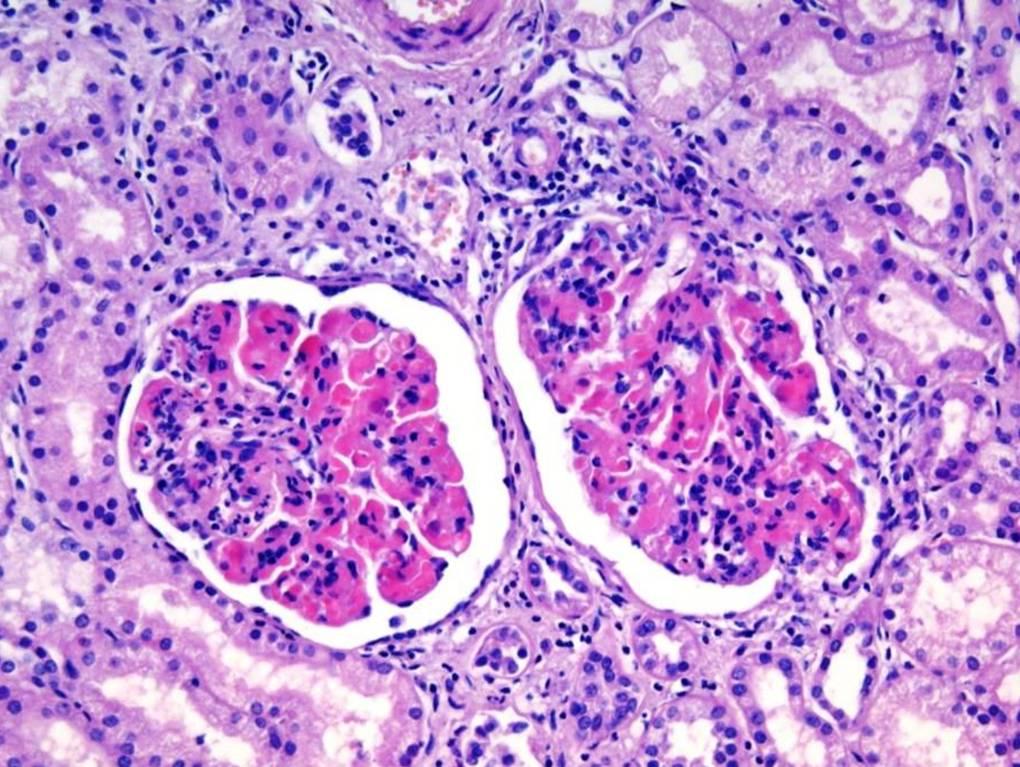

Микропрепараты: Лимфогранулематоз и Нодулярный Склероз

Раздел: Секреты мастерства